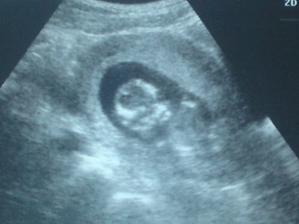

Svatbu jsme měli 16.8.2008 a po 7 dnech po svatbě jsem vysadadila antikoncepci. 25.8.2008 PM a po 3 týdnech zjištění na těhotenském testu dvě čárky :o) Oznámení hned po vyhodnocení testu manželovi - překvapení (asi že to bylo tak rychle) a pak radost. Termín podle PM mám stanovený na 1.6.2009 na den dětí. Doma už máme jednoho prcka a to Kristýnku která bude mít když se ji bráška narodí 4 roky a 3 měsíce. Koupili jsme na veletrhu v Brně nový kočárek a Kristýnka zase dostala novou autosedačku Recaro monza. Jelikož jsou už základní věci po Kristýnce doma, tak tolik kupování zase nebude. Naštěstí se kupovalo všechno na začátku neutrální, tak to využije i Ríša :o) Moc se všichni na toho našeho drobečka který si zatím pěkně lebedí v příšku těšíme. Zatím je vše v pořádku a doufám že bude až do konce těhotenství i porodu :o)

Tak 17.5.2009 v 10:32 hodin se nám narodil Ríša.... je to náš malý poklad 2500g a 44 cm. Uměl si to datum krásně vybrat, aby netrhal partu ostatním členům rodiny. Jeho sestřička Kristýnka je 17.3. a tatínek 17.6. no a Ríša nemohl s tou 17 zůstat pozadu :o)